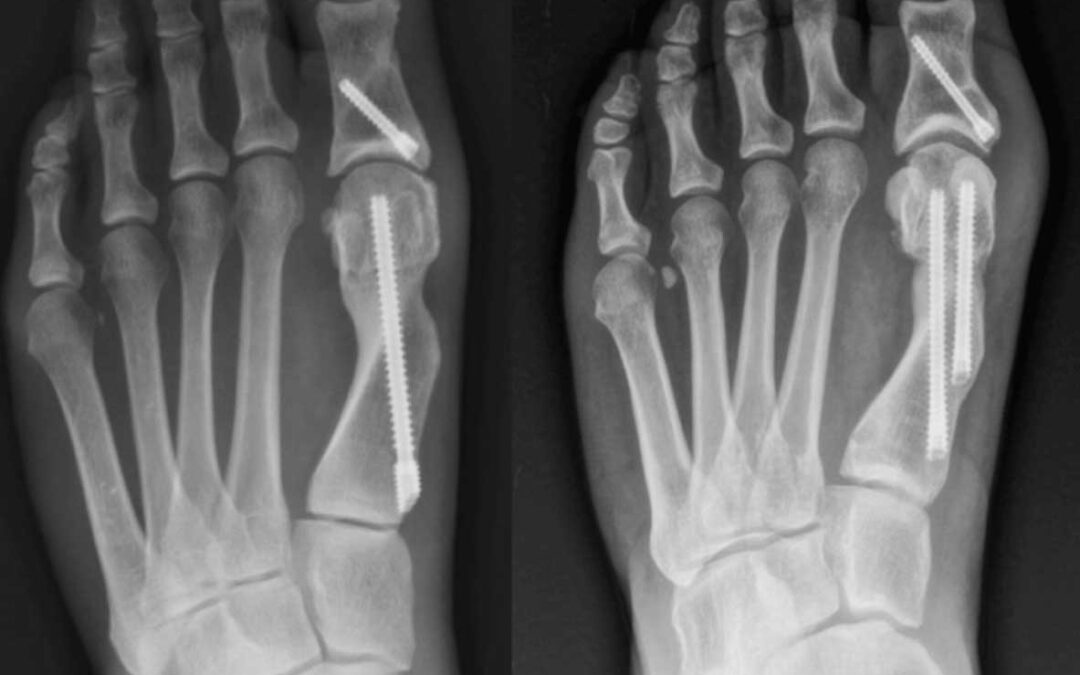

Radiographs demonstrating single-screw (left) and dual-screw (right) fixation following minimally invasive distal metatarsal osteotomy for hallux valgus correction.

Minimally invasive surgery (MIS) for hallux valgus has evolved significantly, with ongoing debate about optimal fixation methods. Fourth-generation techniques typically use 2 metatarsal screws; however, single screw fixation may reduce operative time, radiation exposure, and cost. This systematic review compares clinical outcomes, radiographic results, and complications between 1- and 2-screw metatarsal fixation in minimally invasive hallux valgus correction. Risk of bias was assessed using the Risk Of Bias in Non-randomized Studies of Interventions (ROBINS-I) tool. Primary outcomes included radiographic parameters (Hallux Valgus Angle (HVA), Intermetatarsal Angle (IMA), Distal Metatarsal Articular Angle (DMAA)) and clinical outcomes American Orthopaedic Foot & Ankle Society Score (AOFAS), Visual Analog Scale (VAS), Manchester-Oxford Foot Questionnaire (MOXFQ)). Secondary outcomes included operative details, complications, and revision surgery rates. Five studies met inclusion criteria: 2 clinical (n = 153 patients, 162 feet) and 3 biomechanical studies. Clinical studies showed comparable radiographic correction and patient-reported outcomes between fixation methods. Single screw fixation demonstrated significantly shorter operative time and reduced fluoroscopy exposure. Hardware-related complications requiring removal were higher in 2-screw groups (32% vs. 3% in one study; 1.9% vs. 0% in another). Biomechanical studies revealed that single screw fixation may provide insufficient rotational stability, while 2-screw configurations demonstrated improved construct stability. Current evidence suggests that single screw fixation may reduce radiation exposure, surgical time, and hardware removal rates, but offers reduced biomechanical stability compared to a 2-screw construct in patients undergoing minimally invasive hallux valgus surgery. Current evidence is insufficient to establish definitive recommendations, and fixation strategy should be individualized based on deformity characteristics and patient factors.